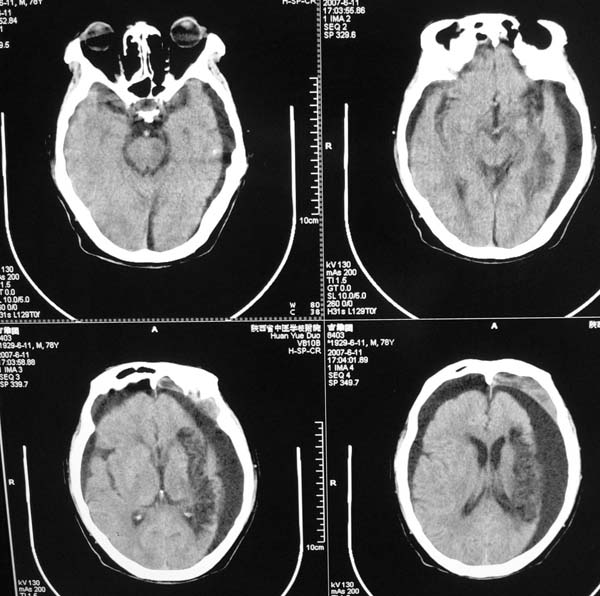

以下是引用star--868在2007-6-15 20:54:00的发言:[br]1.左侧额颞顶部亚急性硬膜下血肿并继续出血 双侧额颞顶部硬膜下积液;[br]2.左颞枕叶、左基底节区脑软化-左侧大脑中动脉栓塞;[br]双侧额颞顶部硬膜下积液应和治疗期间应用高渗脱水剂相鉴别:停用甘露醇后硬膜下积液会逐渐吸收减少,而单纯硬膜下积液无此改变和/或逐渐增多。

以下是引用狙击手在2007-6-15 21:15:00的发言:[br]软化灶就不必说了,主要是混和性血肿的渐变过程。

以下是引用老爱克斯新网客在2007-6-15 20:40:00的发言:[br]1左侧颞叶软化灶,2双侧硬膜下水瘤,3左册硬膜下血肿(多次少量出血),

以下是引用还珠格格在2007-6-16 7:07:00的发言:[br]支持.左侧额颞顶部亚急性硬膜下血肿并继续出血 双侧额颞顶部硬膜下积液;[br]2.左颞枕叶、左基底节区脑软化-左侧大脑中动脉栓塞;